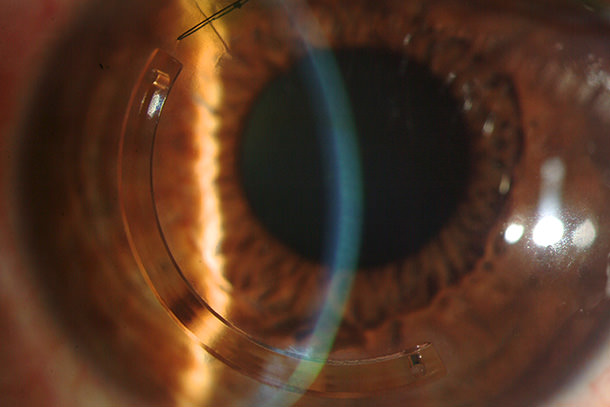

Son segmentos semicirculares de material biocompatible introducidos a nivel del estroma corneal con el afán de centrar la zona de protrusión del cono; se reducen así las aberraciones ópticas inducidas por el queratocono. Se denominan habitualmente según el fabricante: Intacs, Kerarings o Anillos de Ferrara.

Permite un aplanamiento selectivo de la curvatura corneal que reduce las aberraciones ópticas y el grado de defecto refractivo lo cual redunda en una mejora en la calidad visual o mayor tolerancia al uso de lentillas. El efecto esperado no es inmediato. Hay que esperar semanas e incluso meses para que se estabilice el cambio de la forma de la córnea y, en consecuencia, su graduación.